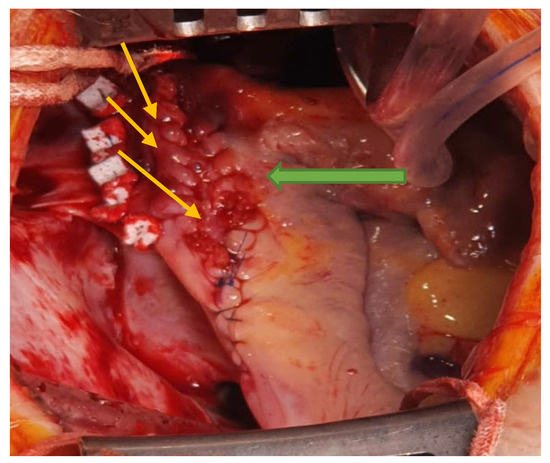

The interatrial defect was exposed through a right atriotomy extended across the cavoatrial junction into the superior vena cava. The examination of the right atrium cavity revealed an atrial septal defect in the proximity of the SVC and both right pulmonary veins draining into the SVC, proximally (Figure 3 and Figure 4).

Figure 3. View of PAPVD in the SVC (pulmonary veins in the SVC—yellow arrow).

Figure 4. Intra-atrial look of the SV-ASD with PAPVD (pulmonary veins ostia—yellow arrows; ASD—blue arrow).